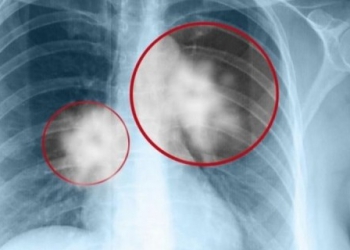

ΠΕΡΙΣΣΟΤΕΡΑΑν και είναι γνωστό ότι το κάπνισμα είναι ο μεγαλύτερος παράγοντας κινδύνου για τον καρκίνο του πνεύμονα, υπάρχουν πολλοί ασθενείς ...